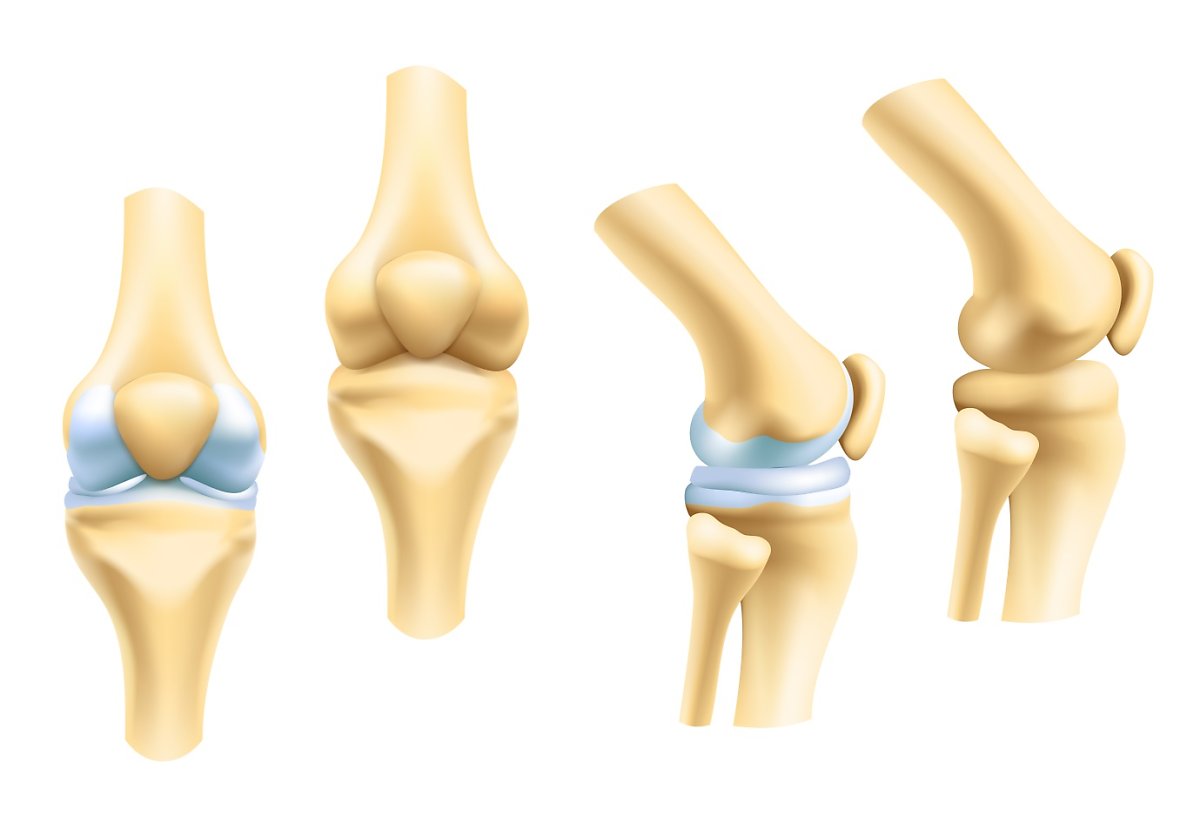

관절 건강에 도움이 되는 성분인 콘드로이친 입니다.나이가 들수록 뼈나 관절 등 신체기관들이 약해지는 건 어쩔 수 없죠. 특히나 무릎관절과 연관해서는 어르신분들이 많이 불편함을 호소하시는데요. 실제로 관절염 환자 중 60% 이상이 40~50대라고 해요. 그래서 최근엔 젊은 층에서도 관절건강에 대한 관심이 높아지고 있습니다. 이처럼 관절 통증 완화 및 연골 재생 효과가 있다고 알려진 콘드로이친 효능에 대해서도 알아보겠습니다.

슬관절염은 슬관절의 연골 파괴와 염증으로 인해 발생하는 관절 질환으로, 통증, 염증, 강직성 등의 증상을 유발해요. 콘드로이친은 슬관절염 환자에서 통증 및 염증을 개선하는 데 도움이 돼요.

콘드로이친 효능은 연골 조직의 주요 구성 요소 중 한가지인 콘드로이틴 성분을 함유하고 있어요. 콘드로이친은 연골 조직의 재생과 보호에 기여하고, 슬관절의 염증을 줄이는 데도 효과가 있어요. 슬관절염 환자들이 콘드로이친을 복용하면, 연골 조직이 보호되어 연골 파괴가 줄어들고, 염증이 감소해서 슬관절 통증이 완화될 수 있어요.

한 번 손상된 무릎 연골은 다시 재생되지 않는다는 특성을 갖고 있고, 노화로 인해 서서히 저하한 체내 콘드로이친은 중년에 이르면 생성할 수 있는 양이 1/20에 불과해요. 콘드로이친은 자연노화로 인해서 관절, 무릎통증, 연골의 노화진행으로 인해 오는 질환에 증상호전을 도와주어 연골세포를 유지시켜주어요. 콘드로이친은 연골세포를 보호해주며 부드럽고 유연하게 유지해서 주어요.